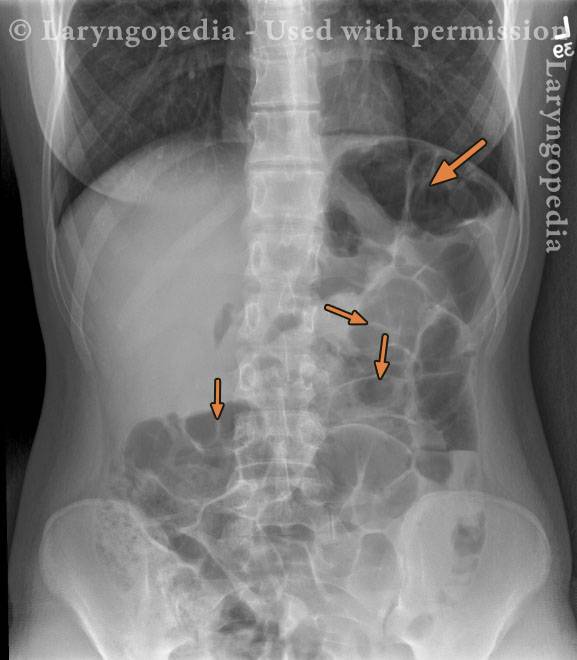

Extensive trapped air (1 of 2)

There appears to be a loop of dilated colon overlying the gastric air bubble (large arrow). Note the absence of air–fluid levels and the preservation of normal mucosal fold pattern (small arrows), without evidence of a “smooth pipe” configuration. Gas is present not only in the stomach and small bowel, but also throughout the colon. Clinically, the patient continued to pass flatus. The subsequent image more clearly demonstrates progression of gas into the descending colon and rectum.